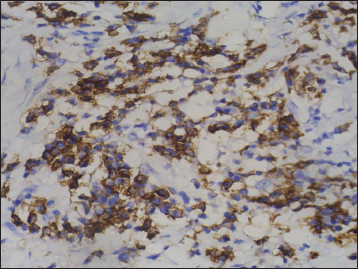

| Figure 9 Immunohistochemistry on subcarinal node showing strong positivity for synaptophysin